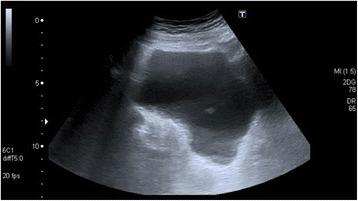

Emphysematous cystitis is a very rare complicated urinary tract infection characterized by air in the bladder wall.

We report two clinical cases of emphysematous cystitis of an 83-year-old Caucasian woman with diabetes mellitus and a 78-year-old Caucasian man with no past medical history. They presented with severe confusion and abdominal distension. Emphysematous cystitis was diagnosed in time with a thorough physical examination, urine analysis and computed tomography. The patients were successfully treated with antibiotic therapy and bladder drainage.